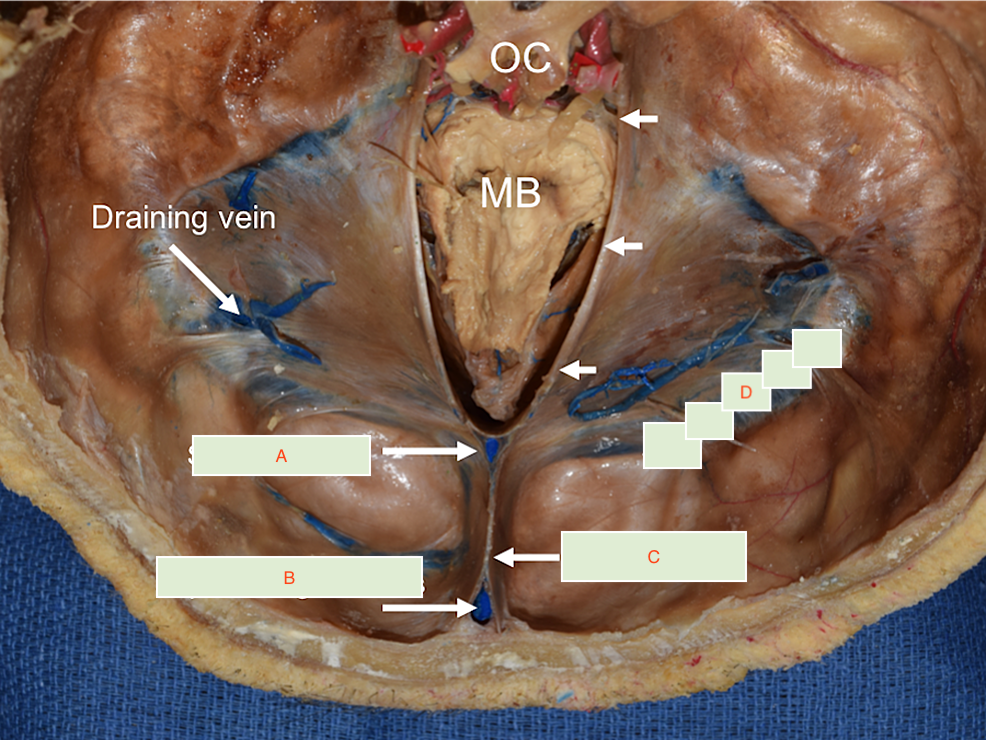

Label A-D